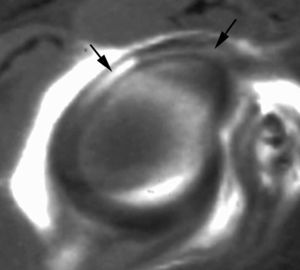

ALPSA (anterior labroliamentous periosteal avulsion)

Al igual que en el apartado anterior, existe también una separación de LG junto con la cápsula y el periostio, pero a diferencia de las lesiones de Bankart o Perthes, el LG se desplaza hacia dentro, por detrás del borde de la glenoides18 (fig. 12). La lesión de ALPSA puede cicatrizar por sinovialización (fig. 12), pero continúa siendo de carácter inestable.

Fig. 12.--ALPSA (anterior labroliamentous periosteal avulsion) agudo (A) y crónico (B). Nótese la separación del labio glenoideo y su desplazamiento posterior y medial por detrás del reborde glenoideo (flecha en A). En una fase crónica el labio glenoideo no se distingue como una estructura separada, sino como un engrosamiento de la unión entre el labio, la cápsula y el periostio (flecha en B).